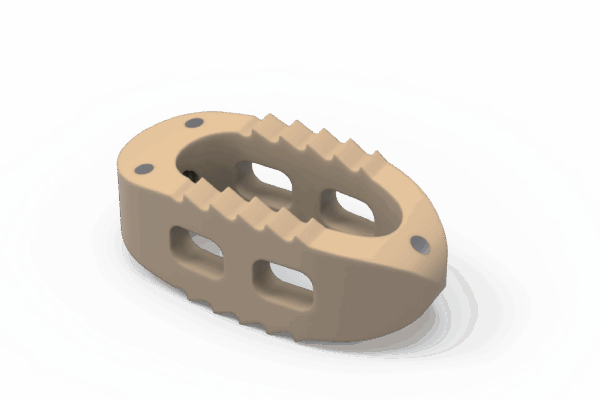

Sistema de cages para fusão intersomática, com diferentes modelos (Coales-P, C, M, T, L e Mesh), em PEEK, com marcadores de tântalo para melhor visualização e adesão óssea.

- Medidas: Diversas opções de altura, largura e ângulo de lordose.

Design anatômico • Radiotransparente • Marcadores de tântalo para visualização • Reduz risco de subsistência